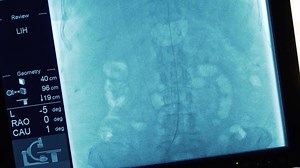

Y-90 Radioembolization Workup …